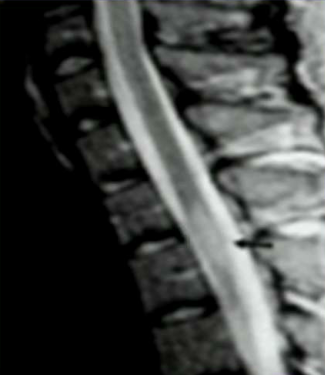

A 28 year old male presents with tingling and numbness in his legs. Over the next day it rises up both legs to the bellybutton. He complains of feeling like their is a tight band around his waist and clumsiness when walking. What do you need to rule out before diagnosing him with MS? What would you expect to see on MRI in a patient with MS?

Transverse myelitis, inflammation of the spinal cord damaging different tracts causing Brown-Sequard syndrome. On MRI you would see a cigar-shaped enhancement in the spinal cord (arrow).